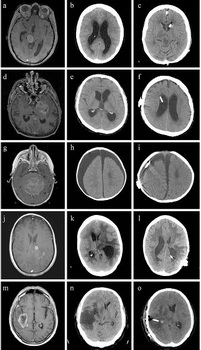

Les effets de la respiration et de la pulsation cardiaque sur le mouvement du LCR ont été étudiés chez 7 sujets sains sous respiration guidée en utilisant l’IRM 2D-PC 3-T asynchrone. Les composantes respiratoire et cardiaque du foramen magnum et de l’aqueduc ont été séparées et leurs fractions respectives de vitesse et de déplacement ont été comparées.